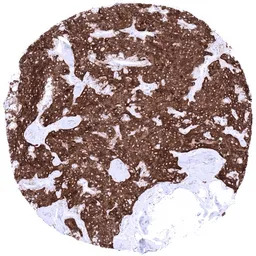

IHC-P analysis of human pancreas tissue section using GTX04371 Synaptophysin antibody [MSVA-462R] HistoMAX.

A strong synaptophysin immunostaining is seen in islet cells of Langerhans.